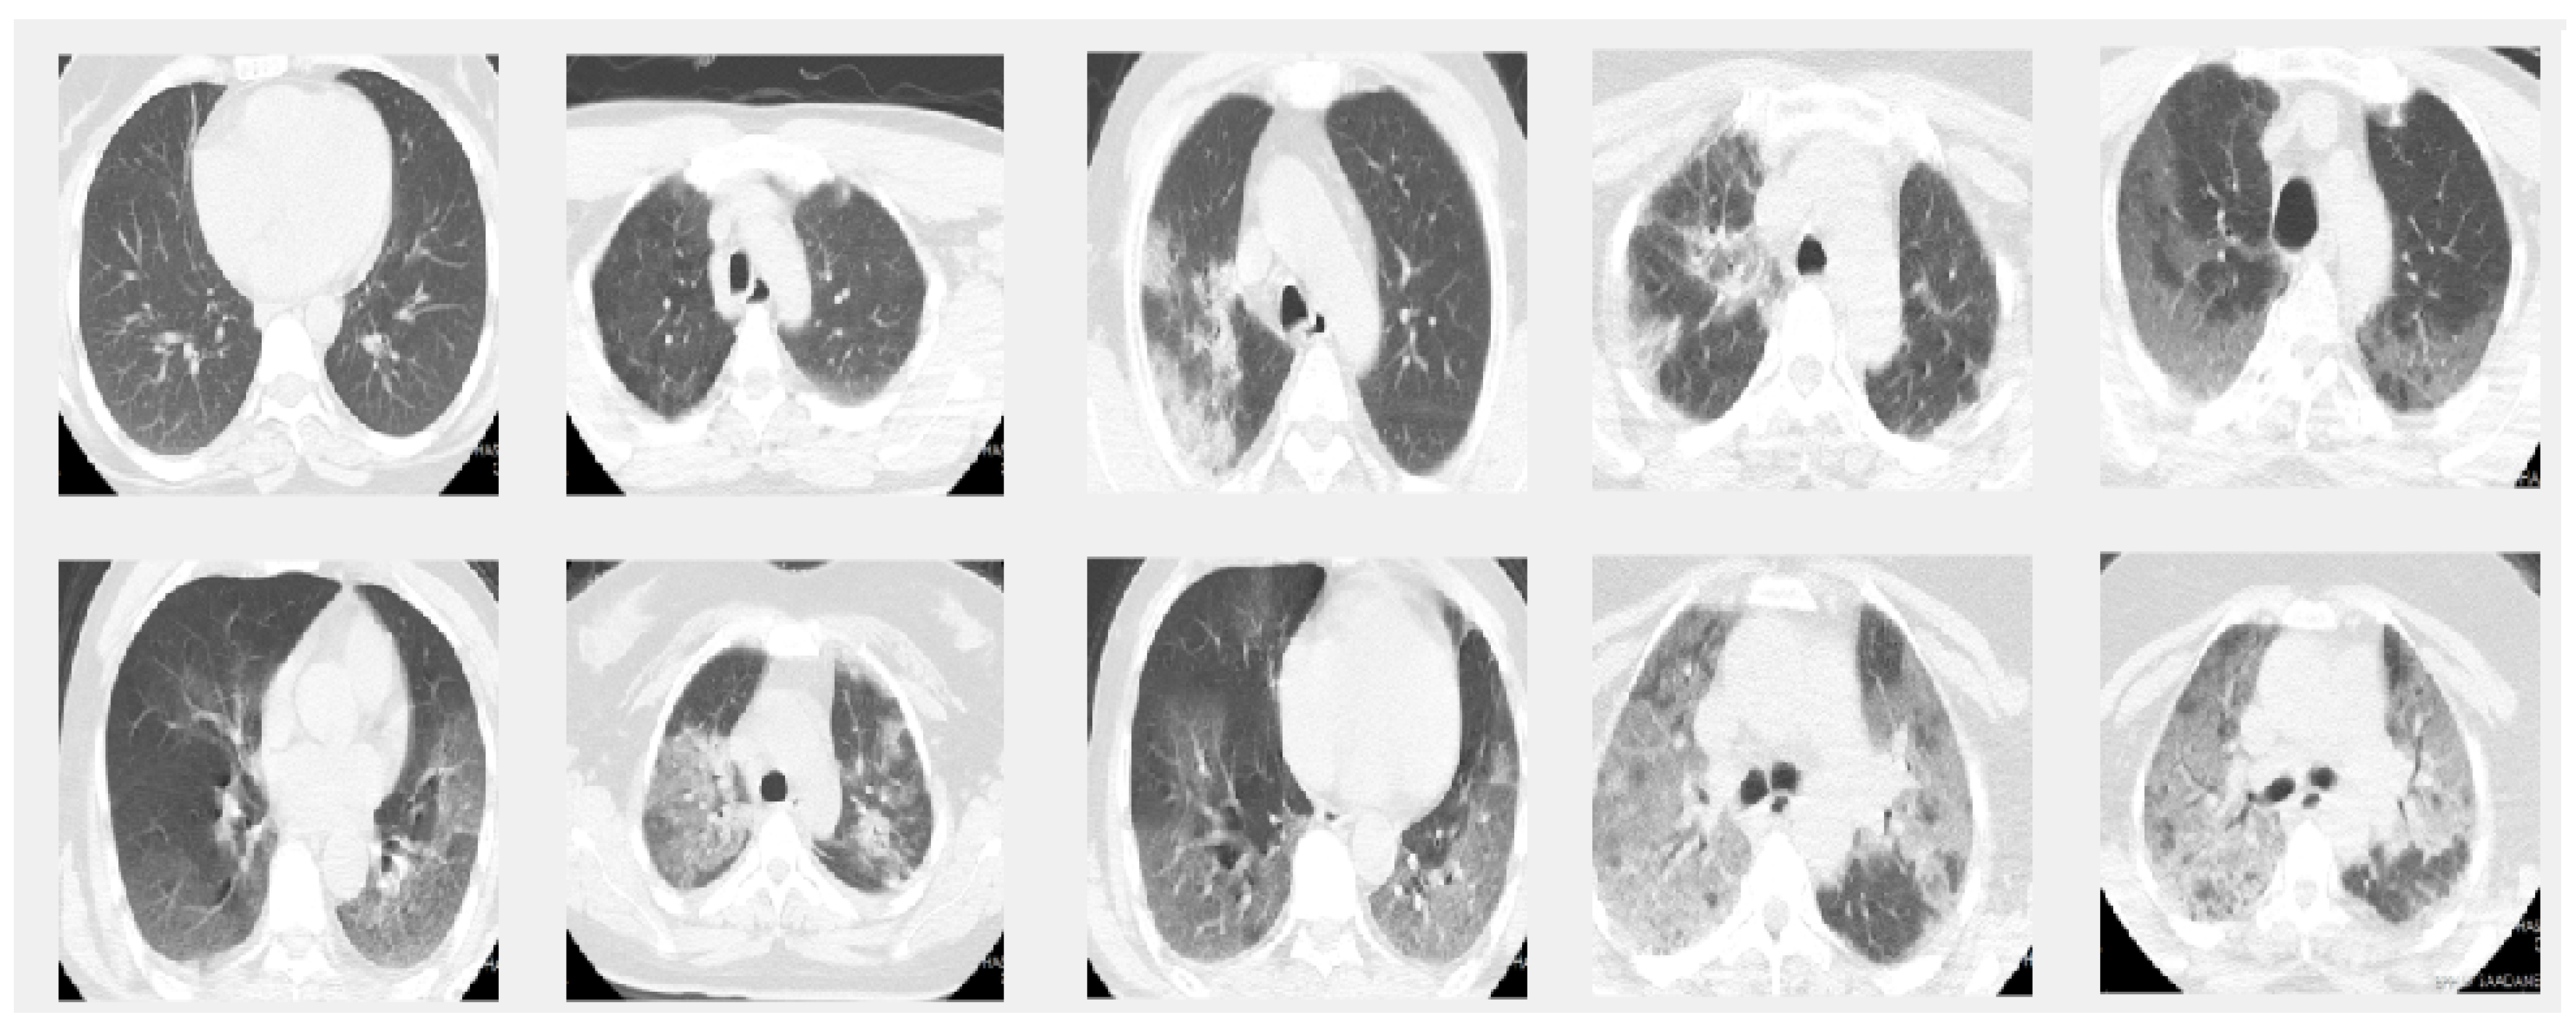

In this paper we used two different datasets which are available online. The first dataset is on chest X-ray images (see Figure 1) and the second on CT scans of lungs (see Figure 2).

4.2. Dataset 2

This dataset is composed of CT scans that were confirmed to have COVID-19. The images were labeled as a function of their infection with COVID-19. This dataset was obtained by [21].

The diagnosis of COVID-19 is based on the most common test, the RT-PCR, and the infection percentage of each slice was identified by two experienced thoracic radiologists. The CT scans were collected from two hospitals: Hakim Saidane Biskra and Ziouch Mohamed Tolga.

Each CT-scan was formed of between 40 and 70 slices. The slices of each CT scan that make up this dataset are those in which the radiologists have the same diagnostic agreement. The number of slices labeled in this set is 3986.

Figure 2. Sample images from the CT dataset. The images in the first row give 5 sample slice images about 0–10–20–30–40% COVID-19 infection in the lungs and the second rows show 50–60–70–80–90% respectively.